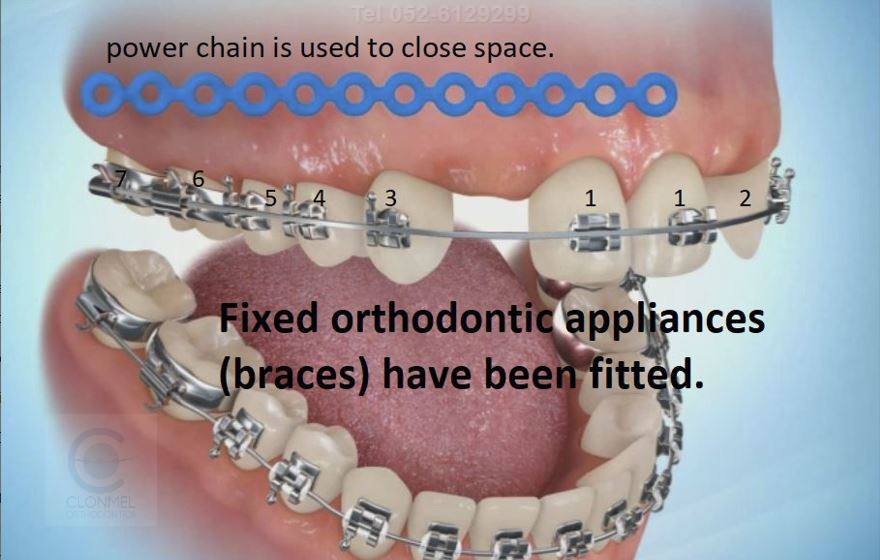

ارتودنسی در بیماران مبتلا به غیبت مادرزادی دندانها نقش بسیار اساسی دارد، زیرا نبود یک یا چند دندان دائمی میتواند باعث برهمخوردن نظم دندانها، ایجاد فضاهای خالی، ناهنجاری در بایت (اکلوژن) و کاهش زیبایی لبخند شود. متخصص ارتودنسی با برنامهریزی دقیق و حرکات کنترلشده دندانها، میتواند تعادل عملکردی و زیبایی دهان را بازگرداند.

در چنین شرایطی، اولین گام در درمان ارتودنسی، بررسی دقیق موقعیت دندانهای موجود و وضعیت رشد فکهاست. پزشک با استفاده از عکسهای رادیوگرافی، مدل فکی و ارزیابی زیبایی صورت، تصمیم میگیرد که آیا فضای دندان غایب باید بسته شود یا حفظ گردد تا بعداً با روشهای ترمیمی (مثل ایمپلنت یا پروتز) جایگزین شود.

در بسیاری از موارد، اگر نسبت اندازه دندانها و فک به گونهای باشد که بستن فضا موجب بهبود هماهنگی فکین و زیبایی شود، ارتودنتیست با حرکات دقیق دندانها فضای خالی را میبندد. در این حالت، دندانهای مجاور بهویژه دندان نیش میتوانند به جای دندان غایب قرار گیرند و سپس با ترمیم زیبایی (مثلاً کامپوزیت یا لمینیت) فرم ظاهری آنها اصلاح شود تا شبیه دندان طبیعی گردد. این روش اغلب در بیماران جوان مناسبتر است، زیرا از کاشت یا پروتز بینیاز میشوند و نتیجهای طبیعی و هماهنگ به دست میآید.

در مقابل، اگر بستن فضا باعث برهم خوردن تناسب دندانها یا لبخند شود، ارتودنتیست فضا را به دقت حفظ میکند تا در آینده بتوان از ایمپلنت یا پروتز برای جایگزینی استفاده کرد. در این مسیر، ارتودنتیست موقعیت و زاویه ریشههای دندانهای مجاور را طوری تنظیم میکند که فضای خالی به اندازه مناسب و با ساختار استخوانی کافی باقی بماند. در سنین پایینتر که هنوز رشد فک کامل نشده، از نگهدارندههای مخصوص یا دندان موقت استفاده میشود تا هم زیبایی لبخند حفظ شود و هم فضا برای درمان نهایی دستنخورده بماند.

- بستن فضای خالی با ارتودنسی: با حرکت دندانهای خلفی به جلو یا تغییر موقعیت دندانهای مجاور، فضای خالی بسته میشود (مثلاً در غیبت لترالهای بالا).

- حفظ فضا برای جایگزینی: در صورت نیاز به کاشت ایمپلنت یا پروتز ثابت، ارتودنتیست فضا را بهصورت دقیق حفظ میکند تا موقعیت کاشت مناسب فراهم شود.